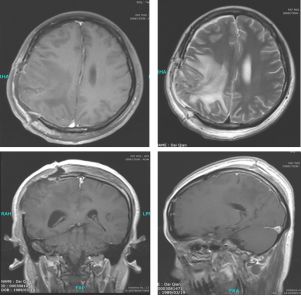

2017年3月26日,患者术后不足3个月,再次因头痛头晕2天入湘雅医院神经外科,行急诊颅脑CT示右侧顶叶囊状新鲜低密度灶,边缘见线样高密度影,周围大片水肿,右侧脑室明显受压变形,中线结构向左偏移,提示局部肿瘤复发,脑疝发生。此时患者胚胎移植后宫内妊娠7+月,患者危重并随时可能发生变化,遂入产科终止妊娠(胎儿胎肺成熟后限期终止妊娠,胎儿状态良好),次日晚突发右侧瞳孔散大,意识障碍,立即予脱水等对症处理后,患者意识恢复。行急诊头颅CT(图4)显示右侧顶叶肿瘤复发,瘤周水肿明显,中线移位。立即入手术室全麻同台行剖宫产术+显微镜下右侧顶叶复发病灶切除术,术后母子平安。

图4. 第二次手术前急诊CT(2017.3.27)